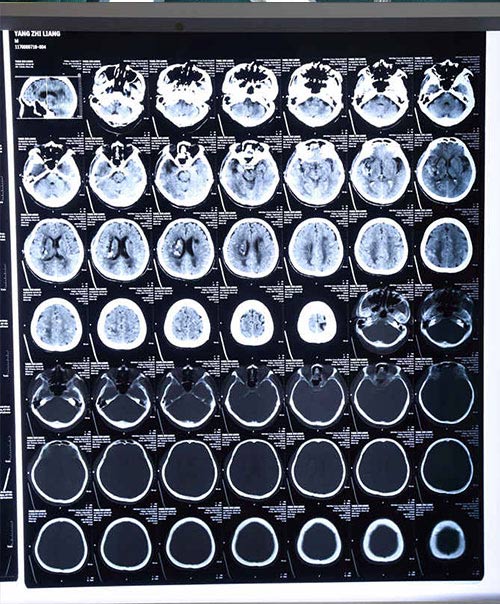

术后三天复查头颅CT:血已经全部清除干净

术后第一天病人意识清楚,讲话清晰,第二天可以吃东西,引流3天后血肿完全清除。目前杨志新老人生命体征平稳,各项指标恢复正常。下一步病人需积极康复,将致残率降到最低。